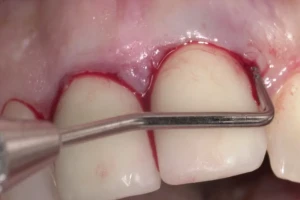

2. Зонды: Используются для измерения глубины карманов и оценки тяжести парадонтальных заболеваний.